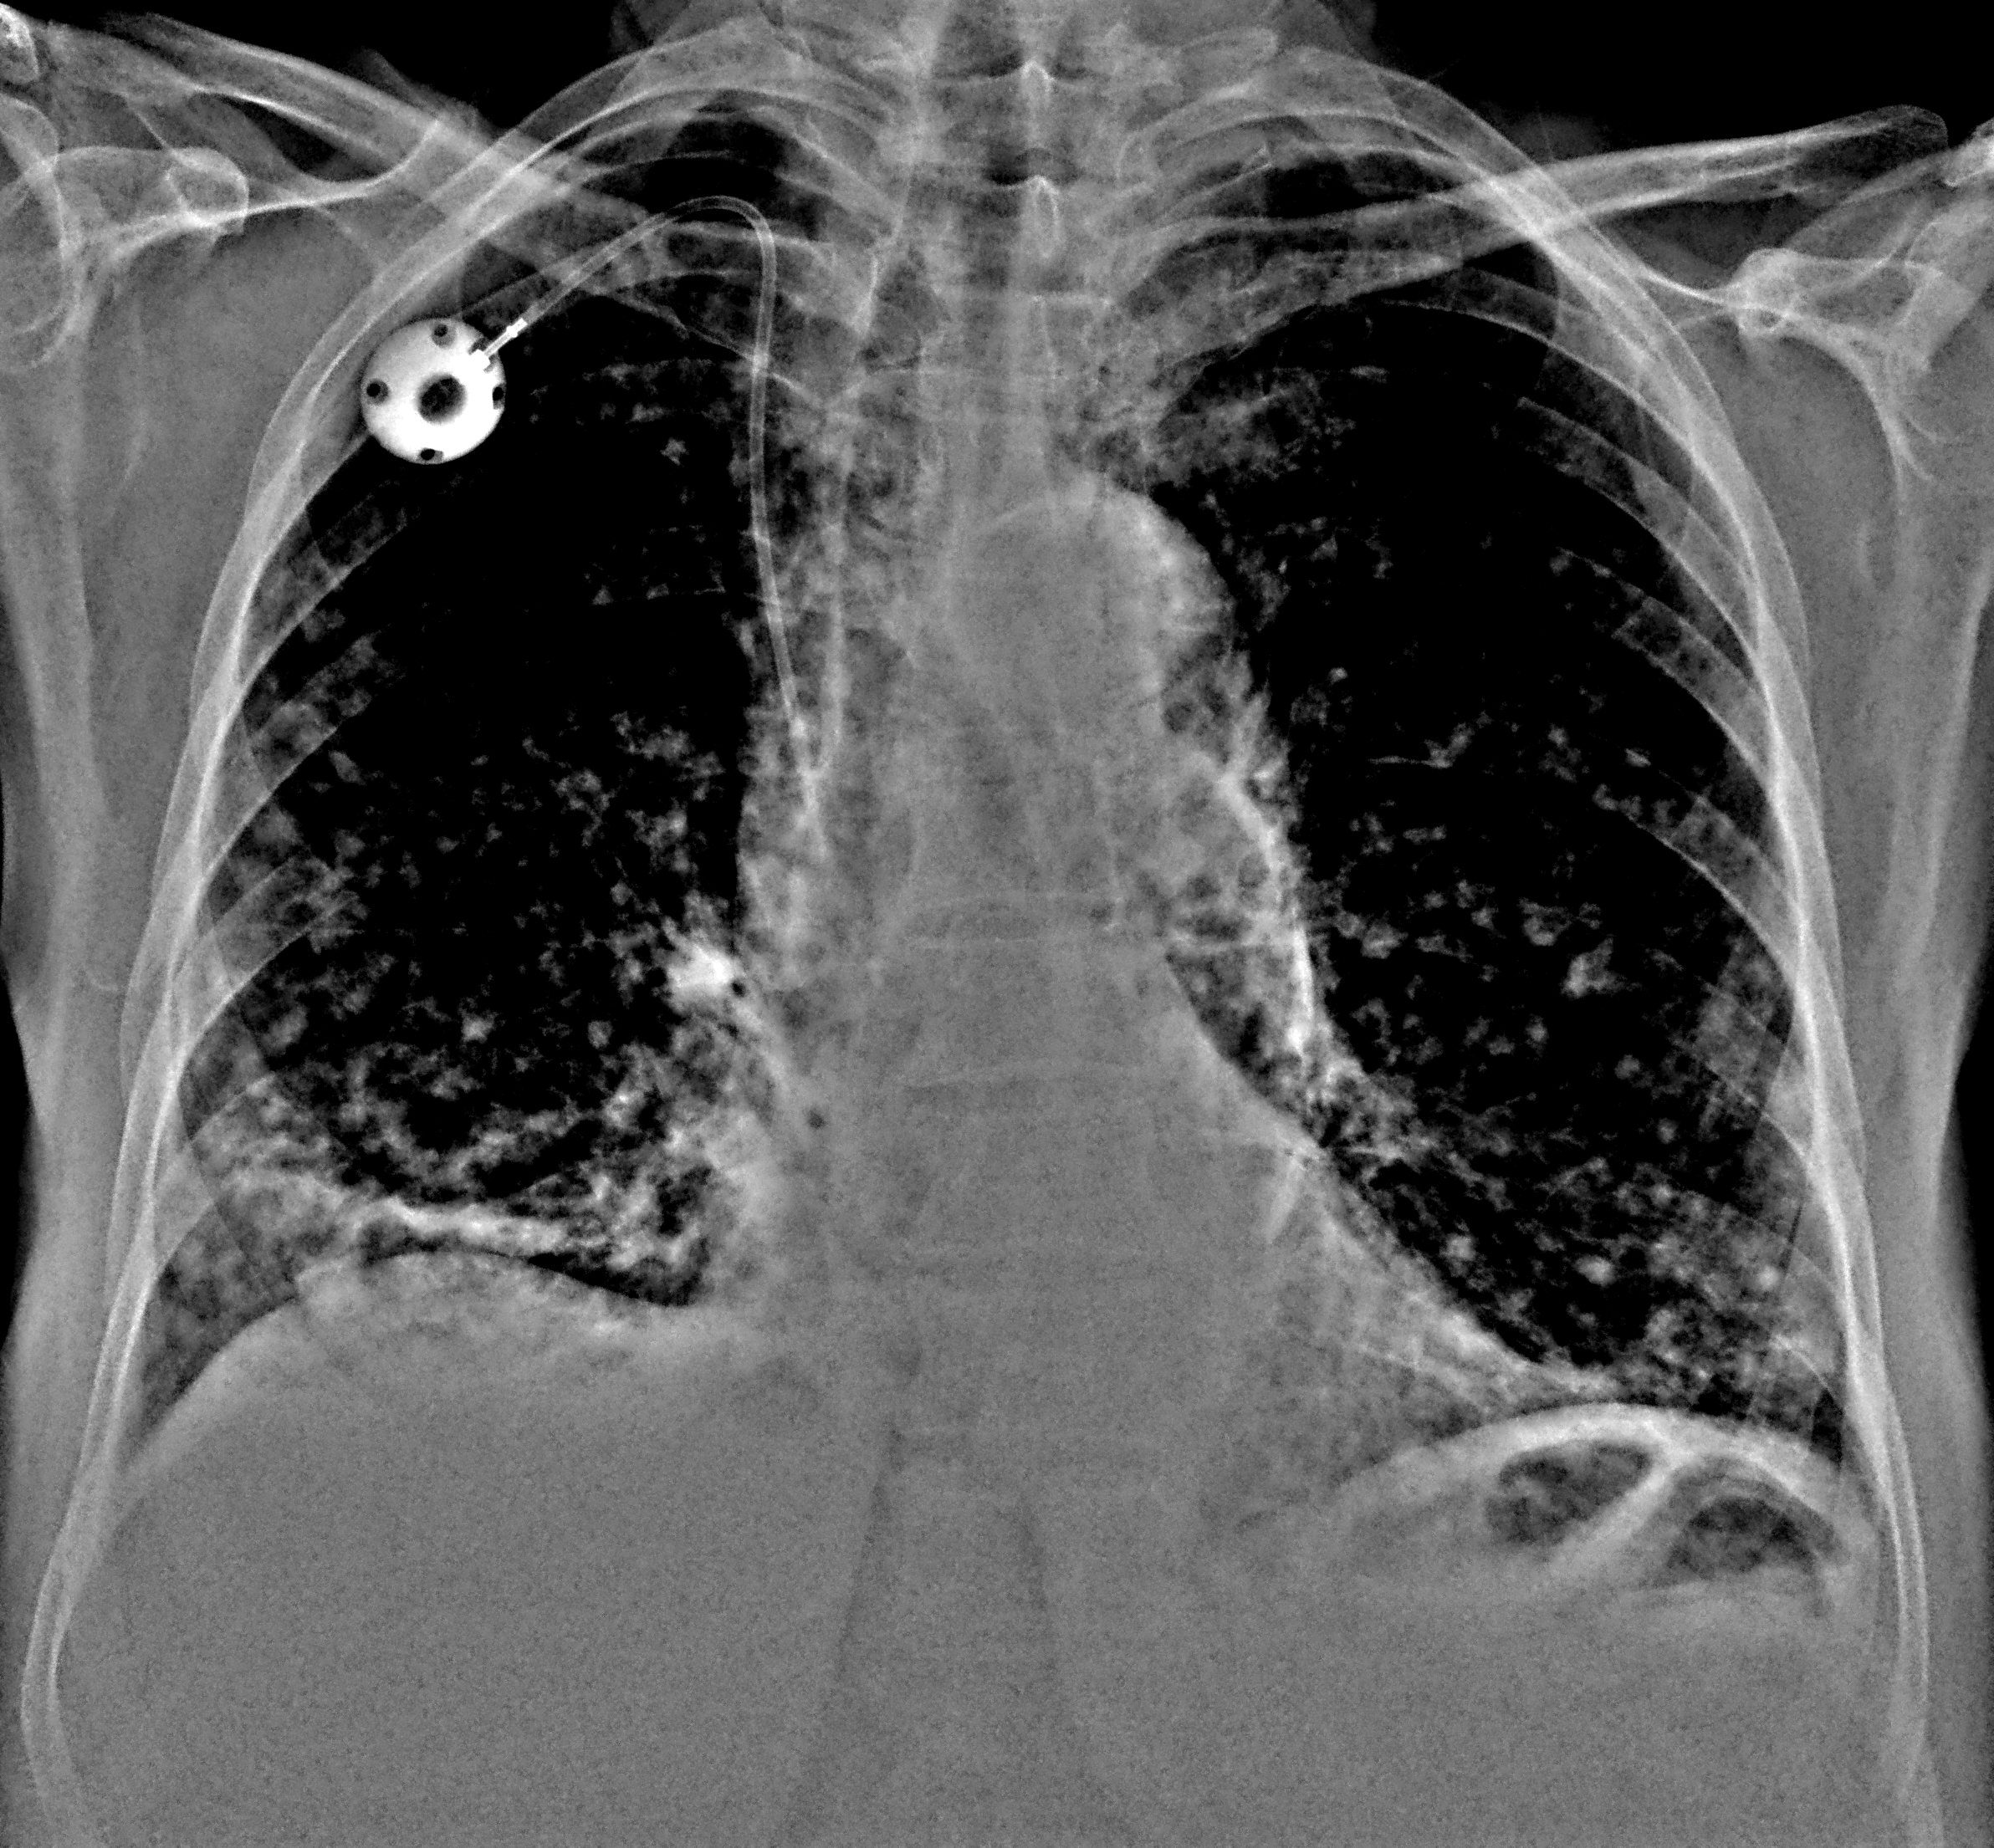

Что такое малоконтрастная рентгенограмма органов грудной клетки